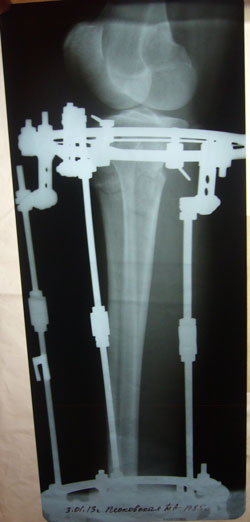

- Диагноз: О-образная деформация ног

- Дата операции.: 01.11.2012

Дата операции 01.11.2012г.

рентгеновские снимки от 03.01.2013г.

2 месяца с момента операции.